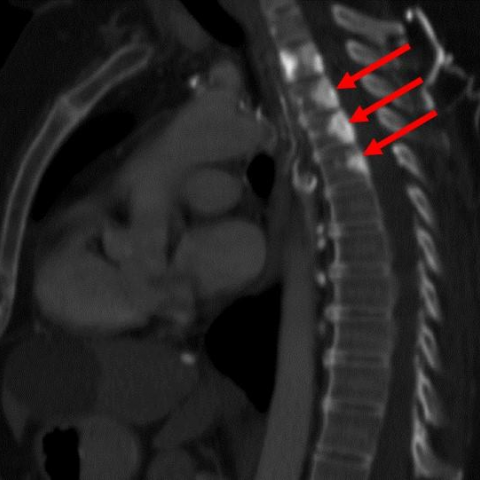

左侧图像:未增强扫描显示椎体密度未见明显异常改变(红箭头指示);

右侧图像:对比增强后,可见椎基静脉孔区域出现三角形的强化影(红色箭头),这是由于静脉淤血和侧支血管形成所致(白色箭头标出)。

CASE诊断:上腔静脉综合征所致的“假性”骨转移(椎静脉丛血管充血)

TIPS:上腔静脉综合征时,导致侧支循环的开放,椎基静脉丛可能会充血,在增强时可能会看到椎基静脉孔区域的明显强化,请勿误诊为转移。